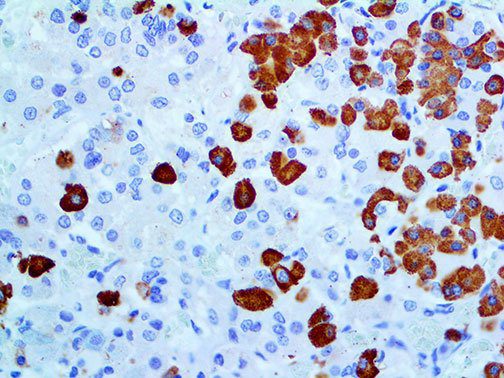

It is the ICU physician who is most likely to witness one of the deadliest manifestations of the abnormal immunological response, the cytokine storm syndrome (CSS). This response is also referred to by some as the cytokine release syndrome (CRS). CSS is characterized by continuous activation and expansion of macrophage and lymphocyte populations, which secrete large amounts of cytokines, causing the cytokine storm. This massive cytokine release is akin to hemophagocytic lymphohistiocytosis (HLH) disease, a syndrome characterized by initial unchecked and persistent activation of cytotoxic T lymphocytes and NK cells.

Clinical and laboratory manifestations of HLH include fever, enlarged liver and/or spleen, neurologic dysfunction, coagulopathy, liver dysfunction, cytopenias (i.e., low levels of erythrocytes, leukocytes, and/or platelets), hypertriglyceridemia, hyperferritinemia, hemophagocytosis, and eventually diminished NK cell activity as the immune system becomes progressively paralyzed. HLH can be familial (primary HLH) or secondary to another disease process (sHLH), such as rheumatic disease, in which it is referred to as macrophage activation syndrome (MAS, characterized by elevated ferritin).